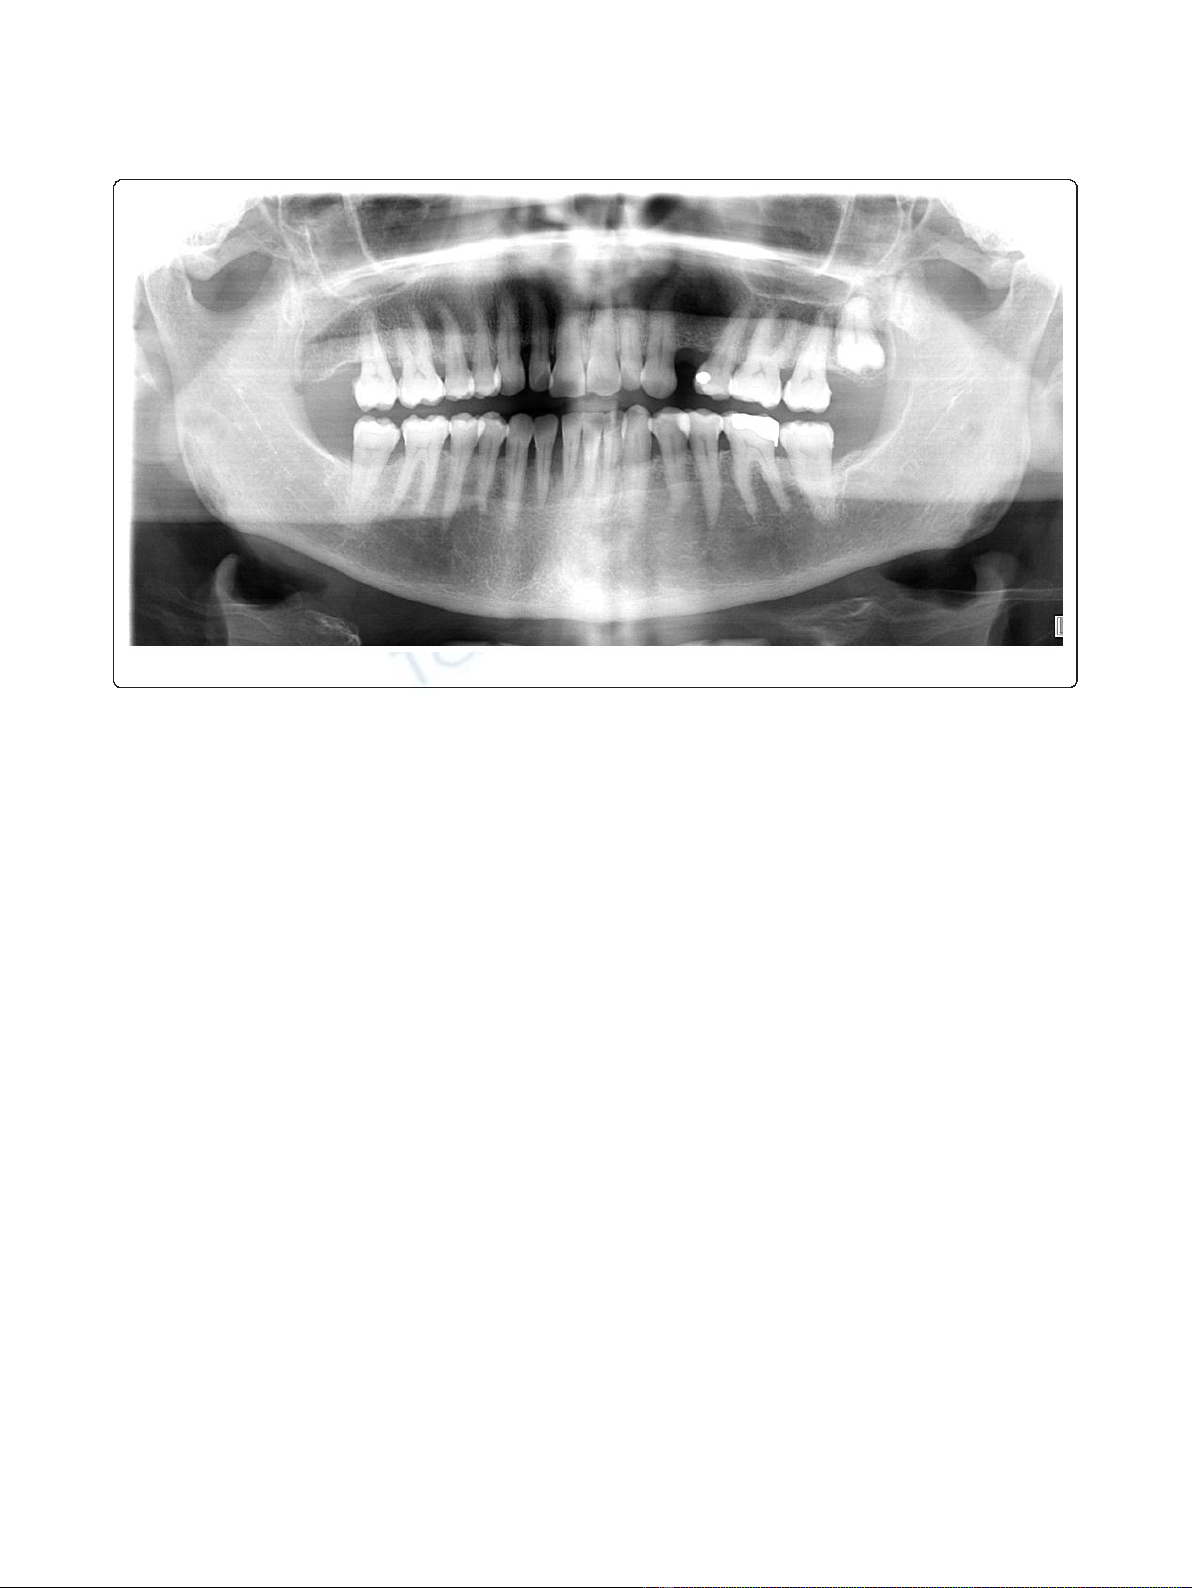

An orthopantomogram of thedentalarchesexcluded

metastases to the jawbones (Figure 5). After multi-disci-

Figure 5 Panoramic radiography showing generalized alveolysis.